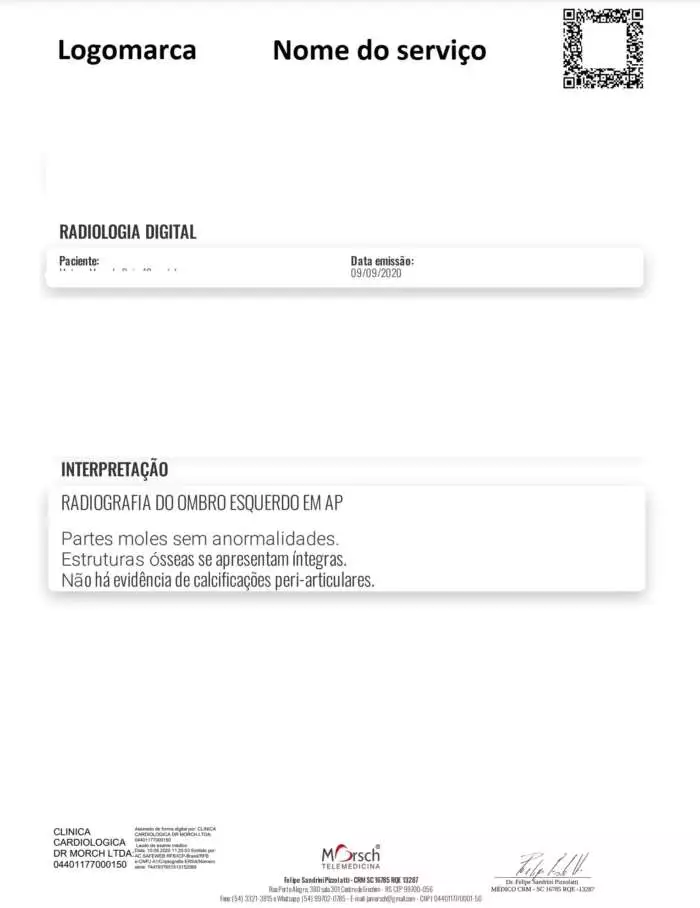

Raio-X: O Que é, Tipos, Resultados E Laudo Do Exame

telemedicinamorsch.com.br

telemedicinamorsch.com.br

Raio-X: o que é, tipos, resultados e laudo do exame